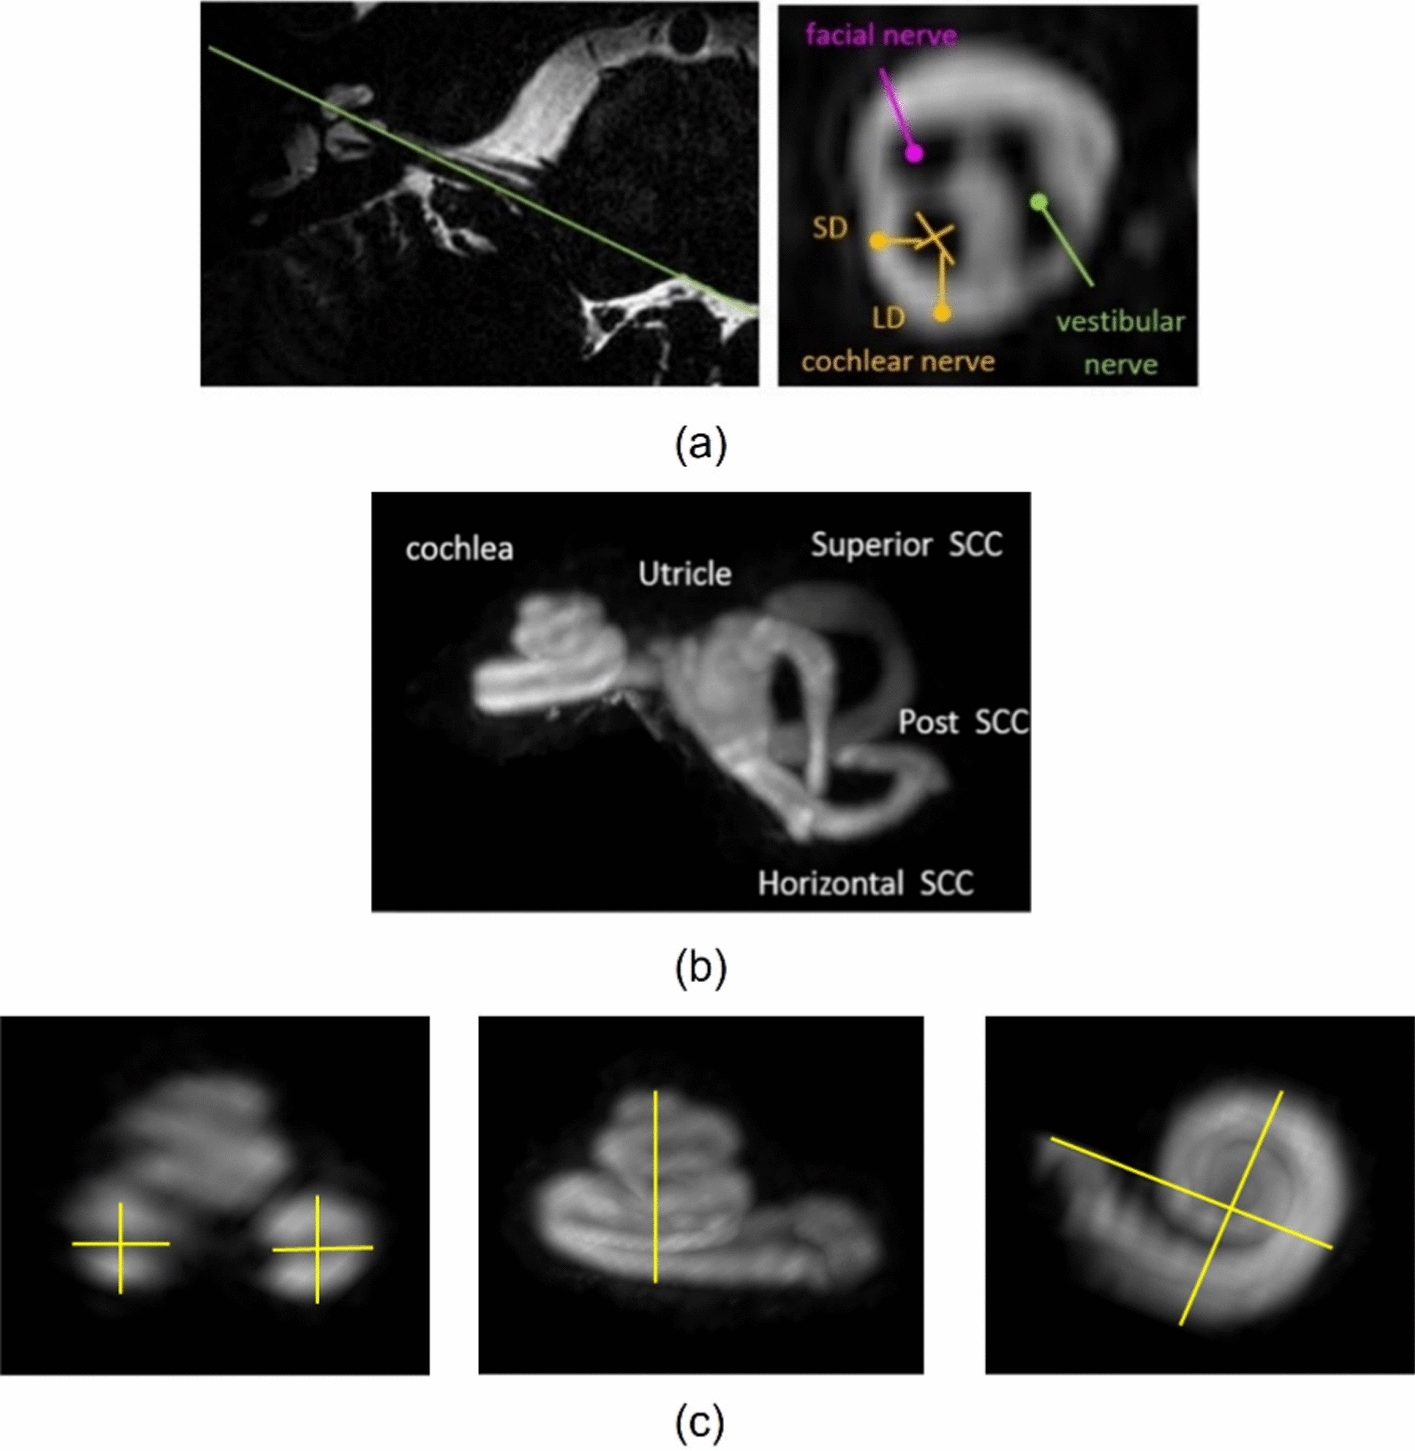

Morphology of the human inner ear and vestibulocochlear nerve assessed using 7 T MRI

To optimize high-resolution 7 T MRI of the cochlea and measure normal cochlea and the cochlear nerve morphometry ...